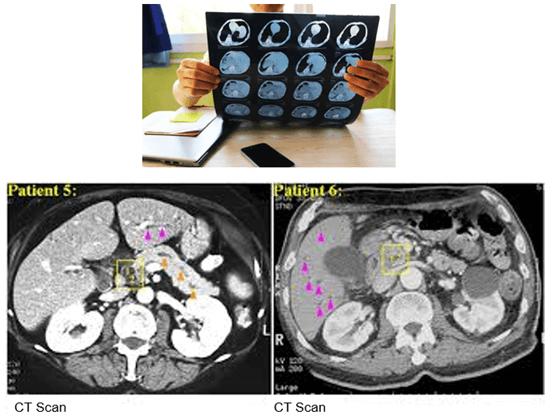

This image shows the effect of the kVp on image contrast. Note the differences between 100 and 120 kVP. The higher the kVp, the lower the contrast, known as low contrast resolution.

These images demonstrate that the thicker the slice, the lower the contrast resolution. Although in general, an image with a thicker slice contains more x-ray photons (or less noise), the partial volume effect can reduce the visibility of smaller objects.

Compare the density of the prosthetic materials in these images all taken at 120 kV. As you can see, gold has the highest Hounsfield units.

It is also possible to adapt the kV values used based on the visualized structure or to use dual-energy protocols. Notice the difference in streaking in these three images.

This image shows the effectiveness of metal reduction artifact software. Notice how much better the resolution is in the image on the right.

Let’s look at the differences in these four images taken at different dual energy levels. Compare the streak artifacts with the 80kV, 140 kV, the mixed acquisition of 140kV and 80 kV and the last at 140 keV.

Faster scanners have improved motion as the patient has less time to move during the scan. This can be accomplished with faster gantry rotation or more x-ray sources. Compare these two images for motion. The image on the right has a much better resolution than the one on the left.

Motion artifacts can be reduced by using special reconstruction techniques. 10% is added to the 360-degree standard rotation. Repeated projections are averaged which reduces motion artifacts. The image on the left shows less motion when this technique is used.